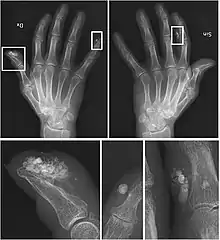

| CREST syndrome (calcinosis and sclerodactyly) | |

CREST causes thickening and tightening of the skin with deposition of calcific nodules ("calcinosis").